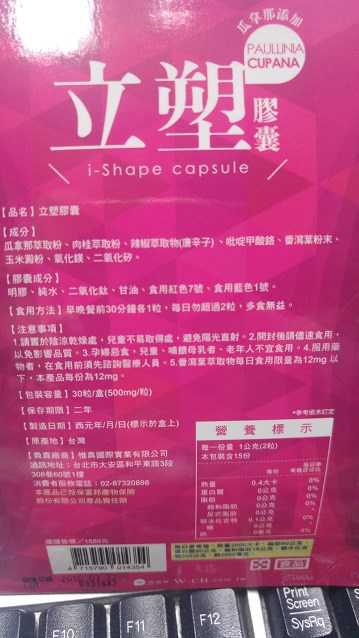

Supercut塑魔纖立塑膠囊的成分有:瓜拿那萃取粉、肉桂萃取粉、辣椒萃取物(唐辛子)、吡啶甲酸鉻、番瀉葉粉末、玉米澱粉、氧化鎂、二氧化矽。

之前上過相關課程,成分表是依照每項成分的多寡來排列順序,排在最前面的就是產品的主要成分!

那我就跟大家分享瓜拿那萃取粉、肉桂萃取粉和辣椒萃取物吧

瓜拿那萃取和辣椒萃取是可以幫助纖體瘦身常見的營養素!

1.「瓜拿那」是原產於亞馬遜流域的一種藤蔓植物,富含酵素可以幫助排便順暢,並且能抑制脂肪分解酵素,此外也有降低食慾的效果喔~~萃取物中含有天然咖啡因,可以提高新陳代謝率以及排出多餘水分!

2.「辣椒萃取物」則是可以幫助體內脂肪燃燒、增加卡路里的消耗,達到防止脂肪積聚的效果

3.「肉桂萃取物」看到肉桂,就想到麥當勞的蘋果派或是手掌麵包,雖然很多人很害怕那味道,但艾哥愛死肉桂了!!!!肉桂在古代被視為是最有價值的東方香料之ㄧ,中世紀時,肉桂的聲望僅次於昂貴的黑胡椒,除了香料和薰香價值, 傳統上肉也被用來治療消化不良、脹氣、關節疼痛、出血和經痛,研究也指出肉桂可以促進新陳代謝喔

食用方式:早晚餐前30分鐘各1粒,每日不超過2粒。(多食無益)

番瀉葉萃取物每日食用限量為12mg以下,